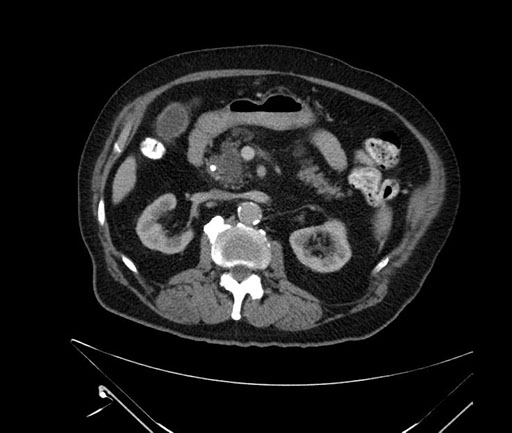

Imaging Analysis

Look through the patient's CT scan to identify any areas of concern for the necessary procedure.

Based on your CT findings, which issue(s) would give reason for "planned slowing down moment(s)" in this case?